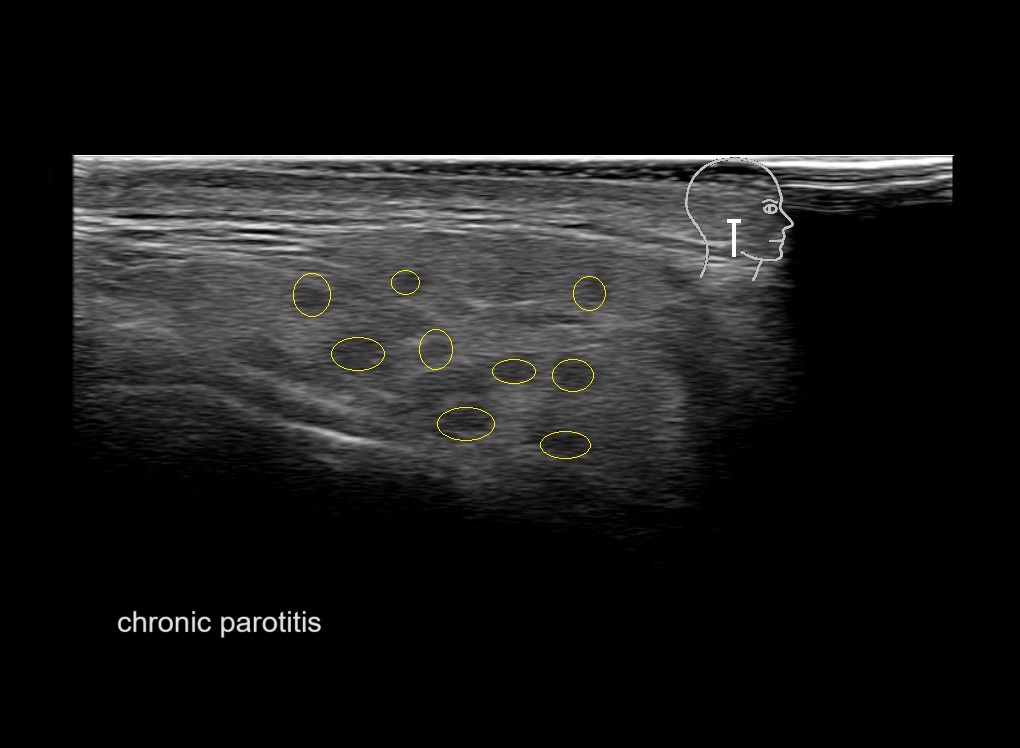

With ultrasound signs of inflammation can be visualized. Edema can be seen as a hyperechoic appearance of the subcutaneous fat, sometimes separated by hypoechoic fluid filled area’s, known as cobblestone appearance. Increased vascularization (hypervascularity) can be seen on colour Doppler. An abscess will appear as a fluid collection appearing as an irregular hypoechoic area with heterogeneous internal echoes and a thickened wall. Posterior acoustic enhancement can be present, and there is vascularity around but not within the mass. Under ultrasound guidance, abscesses can be managed by needle aspirations (18G) under antibiotic cover.

Study the first image to recognize the different layers. If you are sure about the layers, swipe to the second image to view the answer (if applicable).